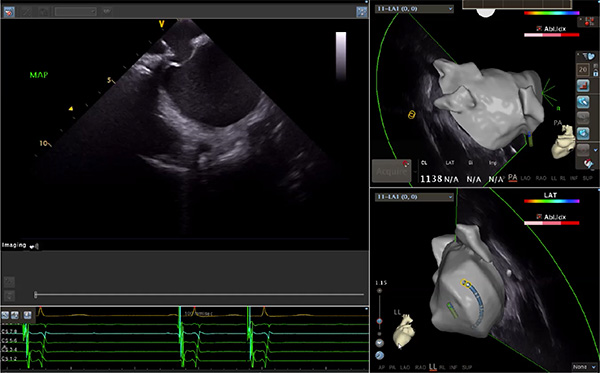

超聲心動圖技術包括常規經胸超聲(TTE)、經食管超聲(TEE)、心腔內超聲(ICE)、超聲聲學造影(MCE)、三維超聲心動圖等,ICE是一種新興技術——將微型的換能器安裝在心導管的尖端,經由外周血管輸送至心腔內部,換能器發射聲波,對心臟及其鄰近組織進行實時高質量成像和(或)血流動力學測定的超聲成像技術。基于不同的技術原理,心腔內超聲導管被分為兩類:機械旋轉式超聲導管和相控陣超聲導管。目前,臨床上主要應用的是相控陣超聲導管,ICE成像通過術者旋轉導管及操縱導管手柄上的兩個旋鈕來完成。

ICE適用的心臟介入手術范圍

隨著心腔內超聲的應用更廣,性能也在逐漸優化,已從二維成像轉變為三維成像,極大增強了引導及可視化能力。二維心腔內超聲支持雙平面或三平面成像,可顯示兩個或三個不同的平面視圖,但醫生需將這些圖像在腦海中重新構建為三維解剖結構。三維心腔內超聲則可直接呈現三維解剖結構圖,便于醫生更輕松地開展手術。按照產品發展方向,預計心腔內超聲還將向更清晰、精準、多功能等方向發展。